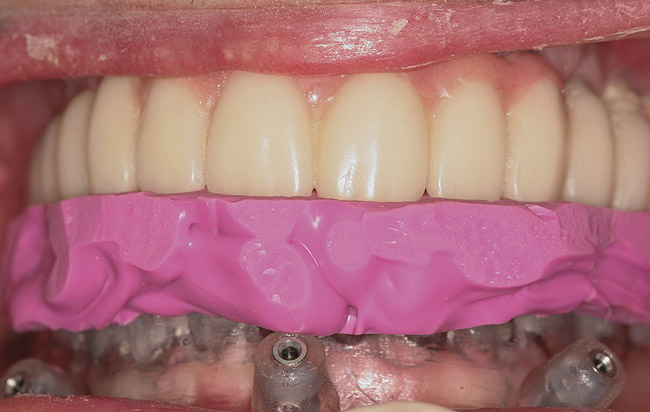

Three types of computer-generated surgical guides are available: tooth-supported, mucosa-supported, and bone-supported. Tooth-supported guides are used in partially edentulous patients; the guide rests on teeth in the arch for accurate fit. Mucosa-supported guides rest on mucosa and are primarily used in completely edentulous patients. Accurate inter-arch bite registrations are important when using these guides to assure precise guide positioning and placement of securing screws or pins prior to implant placement (Figure 1). Bone-supported guides can be used in partially or completely edentulous patients, with their primary use being in completely edentulous applications when ridge atrophy is present and good seating of a mucosa-supported guide is questionable. An extensive full-thickness flap is necessary when using bone-supported guides to expose the bone in the implant sites and adjacent areas for an intimate fit of the guide over the bony ridge.

Figure 1  Surgical index—ie, bite registration between surgical guide and opposing arch—in place prior to insertion of stabilization pins.

Figure 1